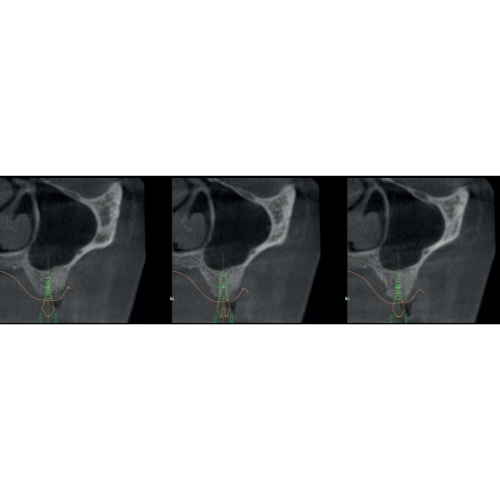

X-MIND® optima 3D represents the perfect combination of advanced hardware technology, enclosed in a lightweight and compact design and next-generation software, RealGuide™ 5.4, bringing the benefits of Artificial Intelligence into every step of patient care, from a precise diagnosis to more effective treatments and patient communication.

- 2D and 3D Imaging